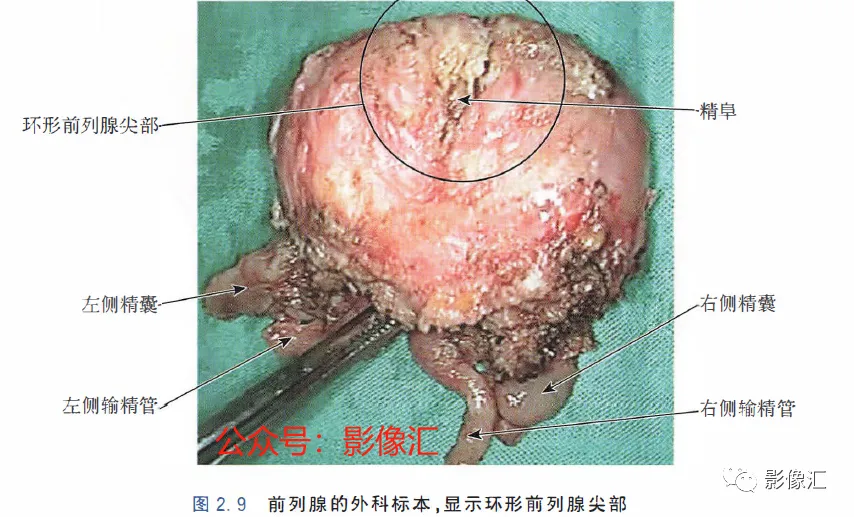

前列腺尖部是用于表示前列腺腺体尾侧(最下方)的术语,与尿道膜部密切接触。前列腺尖部可显示出不同的形态:圆环形或腹侧,背侧或两侧突出(图2. 9和图2.10) ,了解前列腺尖部形态的重要性主要在于两点:(1)前列腺尖部或多或少与EUS(尿道膜部的横纹肌纤维)头侧区域重叠(或覆盖),这些纤维部分融入前列腺尖部(图2.11)。在接受根治性前列腺切除术的患者中,有必要采用能够外翻(exteriorising)和解剖这部分横纹肌纤维的手术技术, 以保持控尿功能(图2.12)。(2)在根治性前列腺切除术中必须避免阳性边缘 。值得注意的是,在尖部水平,腺体组织仅为外周带组织,尖部仅前缘一小部分为AFMS。此外,前列腺尖部构成所谓的梯形区域的顶部,这是众所周知的解剖薄弱区域,在该区域前列腺癌可更易侵犯至前列腺间隙(图2.8)。在其前外侧,前列腺尖部由外括约肌群覆盖,与AFMS及从膀胱颈延伸来的由平滑肌构成的逼尿肌群相融合(图2. 13)。前列腺尖部尾侧与尿道膜部起始部相延续。男性的尿道膜部被认为是位于前列腺尖部和尿道球部之间的尿道部分,长度约为1cm。其内有尿道内括约肌(IUS)和尿道外括约肌(EUS)。IUS从膀胱颈(此处最厚)延伸到尿道球部,沿尾侧方向厚度逐渐减小。IUS环尿道膜部,由双层平滑肌纤维组成,包括内层纵行肌和外部的环形肌(图2. 13和图2. 14)。IUS的神经支配来自自主神经、交感神经和副交感神经系统。下腹下神经丛负责前列腺、前列腺尖部和尿道膜部的所有自主神经支配。其终末支沿内侧走行达耻骨上肌,外侧走行达尿道膜部的EUS,在腹侧构成所谓的阴茎海绵体神经(负责勃起机制)和尿道海绵体神经(负责尿道膜部黏膜的自主神经传入,直接与控尿机制有关(图2 . 13 和图2. 14)。EUS构成横纹肌平面(横纹肌纤维),在尿道膜部水平围绕IUS,在前列腺尖部的前外侧上扩展,并在该水平上构成所谓的EUS围裙(图2. 13)。其肌纤维主要是I 型(即没有肌梭),尽管强度低,但专门负责长时间收缩。EUS的功能在于排尿间期保持尿道腔塌陷,从而防止无意识的尿液渗漏。EUS最厚处位于尿道膜部水平,厚度向头侧逐渐减小,最终构成前列腺围裙。该围裙以Ω(希腊字母“欧米伽”)形围绕尿道膜部,而后正中不包绕, 形成“后正中脊”(图2. 13 和图2. 14)。此外,EUS的部分横纹肌纤维融入到前列腺尖部的下部,位于精阜下方,融入纤维的多少依赖于前列腺尖部形态(图2. 11) 。EUS的神经支配和动脉供血分别来自外阴神经和外阴内动脉。该神经为躯体神经,因此EUS可随意控制。外阴内神经和动脉均向头侧走行,至会阴深横肌处,发出分支支配EUS最尾侧部分,随后形成阴茎背侧神经脊背侧动脉。前列腺尖部与支配EUS的外阴内动脉的分支之间距离为3~13mm (图2. 13)。IUS和EUS构成所谓的控尿被动及内在因素。它们的功能基本上是“塌陷”尿道至“后正中脊”,这样可防止排尿间期无意识的尿液“泄露”(图2.11和2.13)。阴茎海绵体神经在前列腺周围筋膜的后外侧及前外侧走行。手术操作时保留这些外侧神经对于确保前列腺根治术后勃起功能的恢复是至关重要的。会阴体是一纤维肌性结构,难以在解剖上进行评估,其功能是支持所有构成会阴部及支撑盆腔脏器的肌肉及腱膜结构。对于控尿,会阴体形成一固定的底盘,通过将EUS的横纹肌平面压至底盘处,从而可使EUS正确发挥功能,这样在排尿间期可以正确地使尿道塌陷。会阴体由以下结构组成(图2.13)和图2.14)。